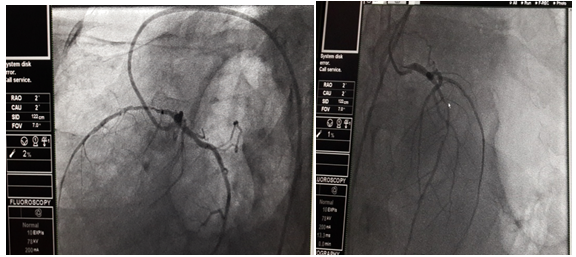

52 years male who is a chronic smoker with systemic hypertension was referred to our center for management of acute ST elevation anterior wall MI. He was managed in outside cardiac center with thrombolysis with streptokinase. Patient gives the past history of thoracotomy for repair of diaphragmatic hernia. On clinical examination, vitals were stable. Cardiovascular system (CVS) examination: Apex localized to the right 5th intercostal space. There was decreased air entry over the left inter/infrascapular and axillary lung zones. Chest X-ray was suggestive of elevation of left dome of diaphragm with fundus air shadow with dextrocardia (apex pointed to right side with right sided aortic knuckle) (Figure 1). Electrocardiogram was suggestive of dextrocardia (decreasing voltages from V1-V6) as shown below in Figure 2. Echocardiography showed dextrocardia with mild LV systolic dysfunction (LVEF-40%) with regional wall motion abnormality (RWMA) along LAD territory. Troponin I was positive (0.1ng/ml) and CPK-MB was 80IU/L. Coronary angiography was done with Judkins left and right (JL and JR) 3.5×6F diagnostic catheter. It revealed single vessel disease over mid-LAD (90% stenosis) as shown in Figure 3. Subsequently, left coronary artery was hooked with EBU 3.5×6F catheter. BMW wire was used to cross the lesion followed by multiple predilatations with 2×10 mm balloon. Successful PCI was done with deployment of NOVUS drug eluting stent (Sirolimus eluting stent) 2.75×32mm at 14atm.pressure as illustrated in Figure 4. 150 ml of contrast (non-ionic, iso-osmolar Iohexol) was used during the procedure. TIMI III flow was achieved. During shifting of the patient to the coronary care unit (CCU), patient had accelerated hypertension with increasing shortness of breath and desaturation(Sp02<90%) which was suggestive of acute pulmonary edema. The patient responded with diuretics, nitroglycerin infusion, morphine and high flow oxygen support within hours. Patient was discharged on fourth day in stable condition.

Figure 3: Coronary angiography shows mid-LAD 95% stenosis.